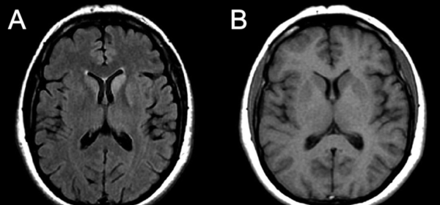

图1

核磁共振在入学

轴向fluid-attenuated反转恢复图像(一个)显示信号hyperintensity尾状核头部,在离开豆状核和内侧额叶皮层双边。轴向t1加权图像(B)是正常的。